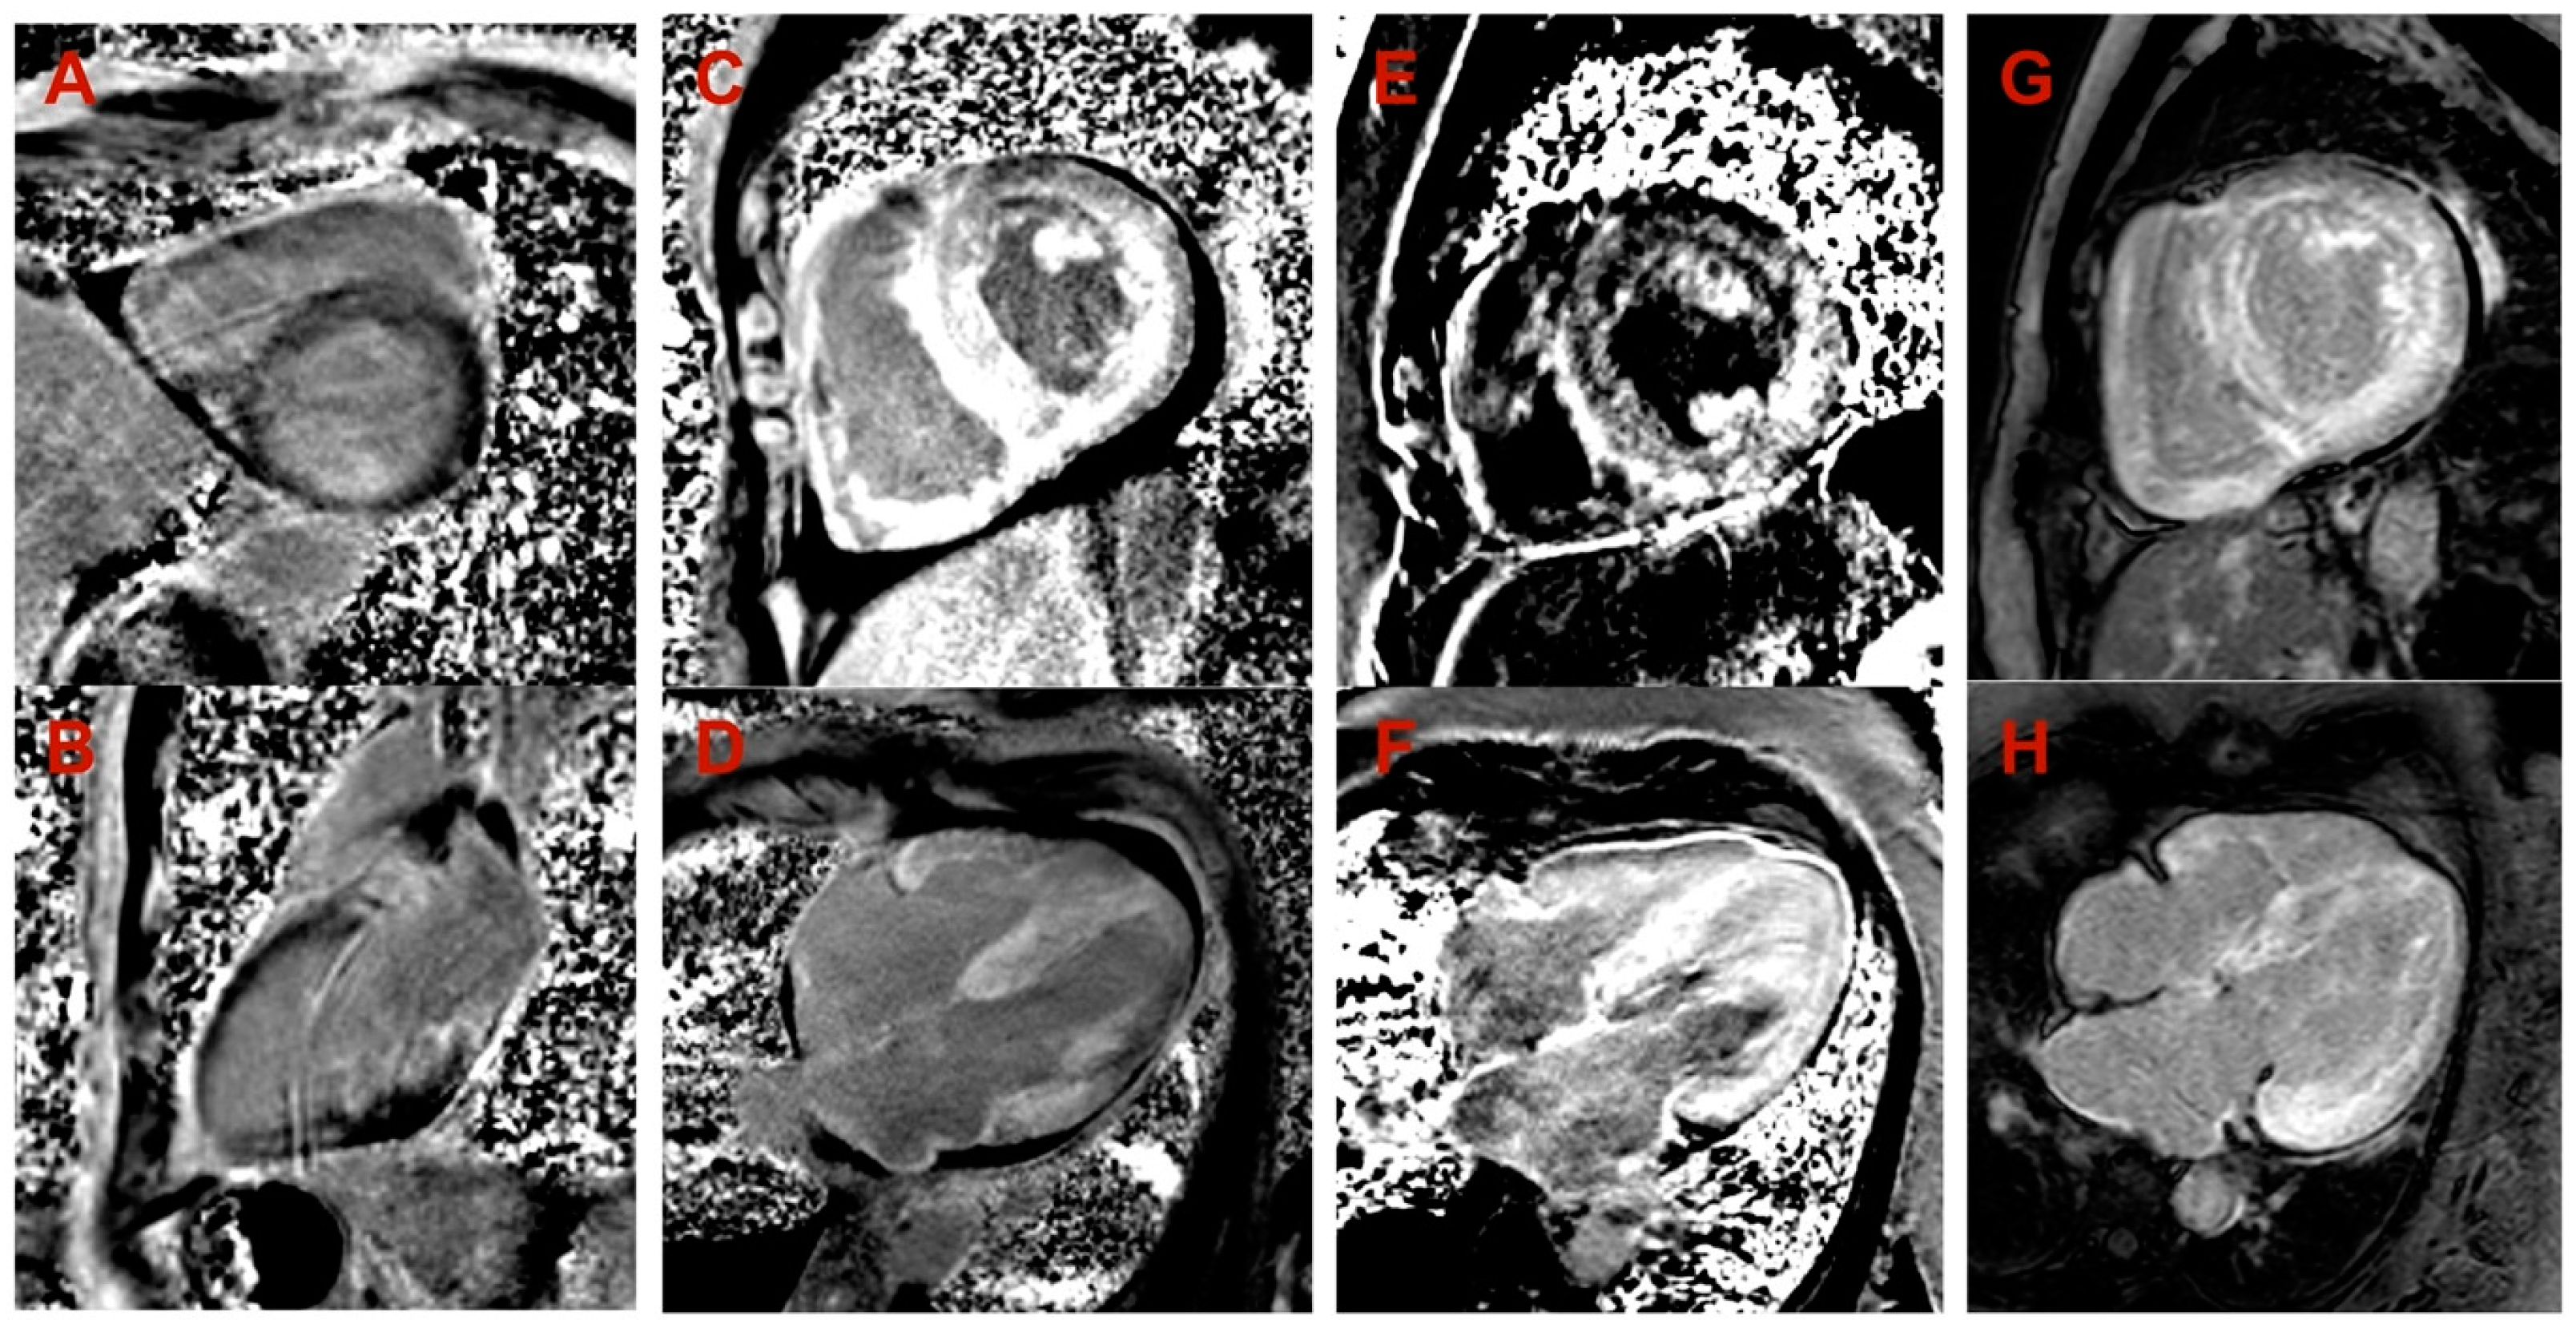

| Proband No. | 1 | 2 | 3 | 4 |

|---|---|---|---|---|

| Zygosity of NM_000371.3:c.302C>T, NP_000362.1:p.(Ala101Val) variant in TTR | Homozygous | Heterozygous | Heterozygous | Heterozygous |

| Sex | Male | Male | Female | Female |

| Age of onset of symptoms (years) | 44 | 74 | 50 | 72 |

| Age at diagnosis (years) | 49 | 77 | 57 | 74 |

| NYHA class of heart failure | III | III | III | III |

| Positive family history | Mother at an older age and aunt on mother‘s side had heart disease | Brother had heart disease | Mother had heart disease, grandmother on mother‘s side had sudden death | Mother and brother died of stroke at an older age |

| Low QRS voltage | - | + | + | + |

| Pseudoinfarct pattern on ECG | - | - | - | - |

| Conduction disturbances | RBBB, LAFB | LBBB | - | LBBB |

| Atrial fibrillation | - | + | + | - |

| LV hypertrophy | Concentric | Concentric | Concentric | Concentric |

| Maximal wall thickness (mm) | 13 | 21 | 14 | 19 |

| LVEF (%) | 67 | 10 | 55 | 40 |

| Restrictive LV filling pattern | - | + | + | + |

| Increased RV wall thickness | + | + | - | + |

| Pericardial effusion | - | + | - | - |

| Cardiac MRI LV hypertrophy | Asymmetric (predominantly in transventricular septum) | Symmetric | Symmetric | Symmetric |

| Cardiac MRI maximal wall thickness (mm) | 16 | 19 | 14 | 20 |

| Cardiac MRI LVEF (%) | 77 | 45 | 50 | 44 |

| Cardiac MRI LGE | Midmyocardial LGE in LV septum and inferior wall | Diffuse subendocardial LGE in LV and RV | Diffuse midmyocardial LGE in LV and RV | Diffuse subendocardial LGE in LV and RV |

| 99mTc-PYP bone scintigraphy | Grade 0 | - | - | Grade 3 |

| Histological confirmation | Amyloid deposits, likely non-specific reaction to transthyretin on immunohistochemistry in bone marrow trepanobiopsy and endomyocardial biopsy | TTR amyloid deposition in adipose tissue biopsy | TTR amyloid deposition in endomyocardial biopsy | - |

| NT-proBNP (pg/mL) * | 474 | 11401 | 3368 | 2471 |

| Troponin I (ng/L) * | 111 | 95 | 65 | 45 |

| Polyneuropathy | + | - | - | + |

| Chronic kidney disease | - | + | + | - |

| Gastrointestinal manifestation | + | + | - | - |

| Carpal tunnel syndrome | - | - | + | + |

| Biceps tendon rupture | - | NA | - | - |

| Follow-up after diagnosis (years) | 3 | 2 | 3 | 1 |

| Outcome | Death at age 52 due to pneumonia complications | Death at age 79 due to colon adenocarcinoma | Death at age 60 due to heart failure decompensation | Death at age 75 due to heart failure decompensation |

| Family segregation analysis | NA | Variant identified in phenotypically negative 47-year-old daughter | Variant identified in phenotypically negative 33-year-old daughter | NA |